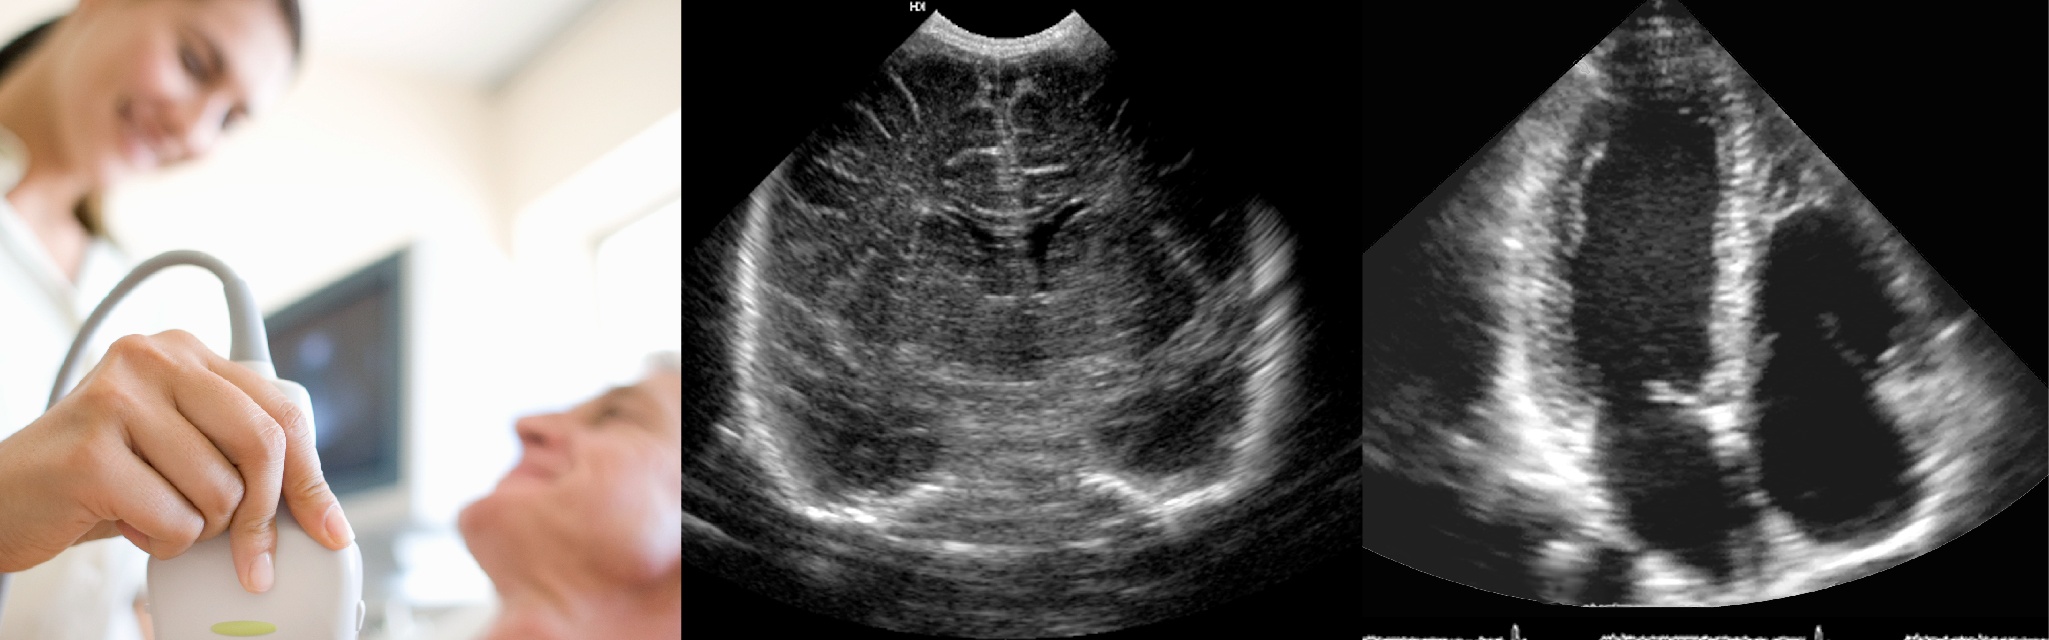

심장 초음파란?

심장초음파는 심장의 움직임과 구조를 평가하는 검사로 심장의 해부학적 구조, 심장

기능, 심장 내 압력 등을 측정할 수 있습니다.

검사는 상의를 벗고 가슴에 심전도 전극을 부착한 후, 탐촉자에 젤을 바르고 시행됩니다.

20~30분 정도 소요되며, 인체에 무리를 주지 않는 비침습적 검사로 별도의 준비 없이 시행됩니다.